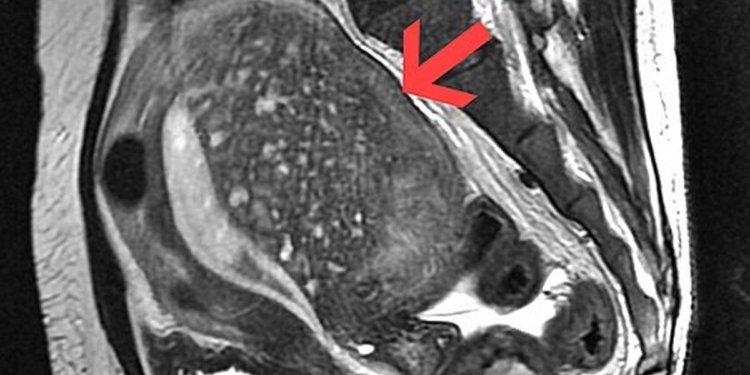

Despite being relatively common, adenomyosis remains under-recognised, with many women receiving a diagnosis only after years of symptoms